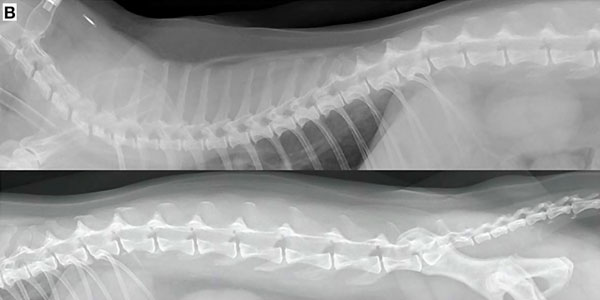

Истончение костей у кошек: причины и решения